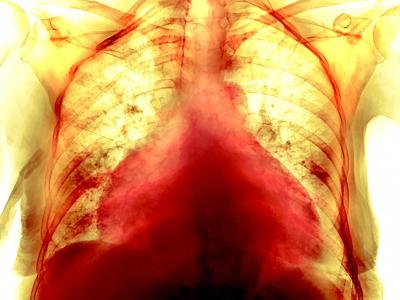

COVID-19如何伤害我们的心脏?科学家早就

这张彩色胸腔X光影像显示一名74岁女性COVID-19病患的肥大心脏。有些病患从COVID-19...